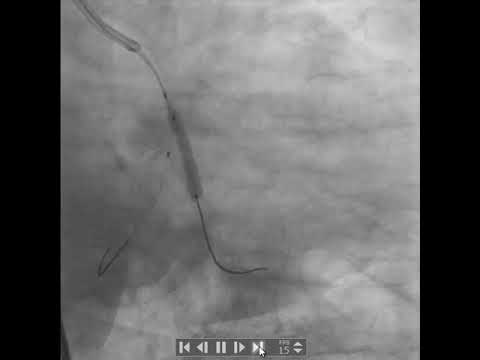

PCI to LCX-OM bifurcation using DK crush technique (case 5)(Delta Cath.Lab-Zagazig)

CRUSH TECHNIQUE STENTING OF LAD - D1 BIFURCATION

DK Crush PCR EAPCI Animation